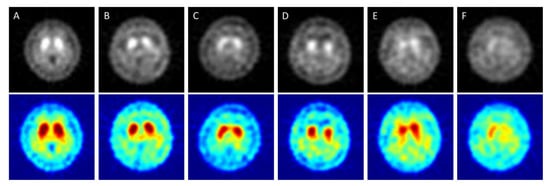

2. Materials and Methods

2.2. The Imaging Conditions of 99mTc TRODAT-1 SPECT